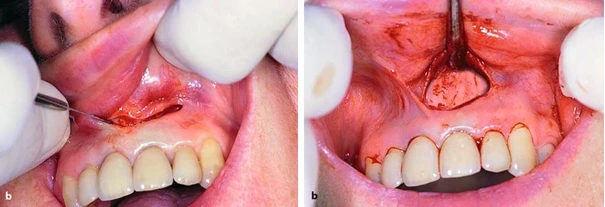

Hình ảnh X quang cho thấy nang quanh chóp răng cửa giữa mà nguyên nhân do điều trị nội nha chưa tốt. Chưa xuất hiện hình ảnh lỗ rò trên lâm sàng.

Đường rạch mở vạt bán nguyệt, bóc tách vạt toàn phần bộc lộ xương vùng chóp răng tương ứng